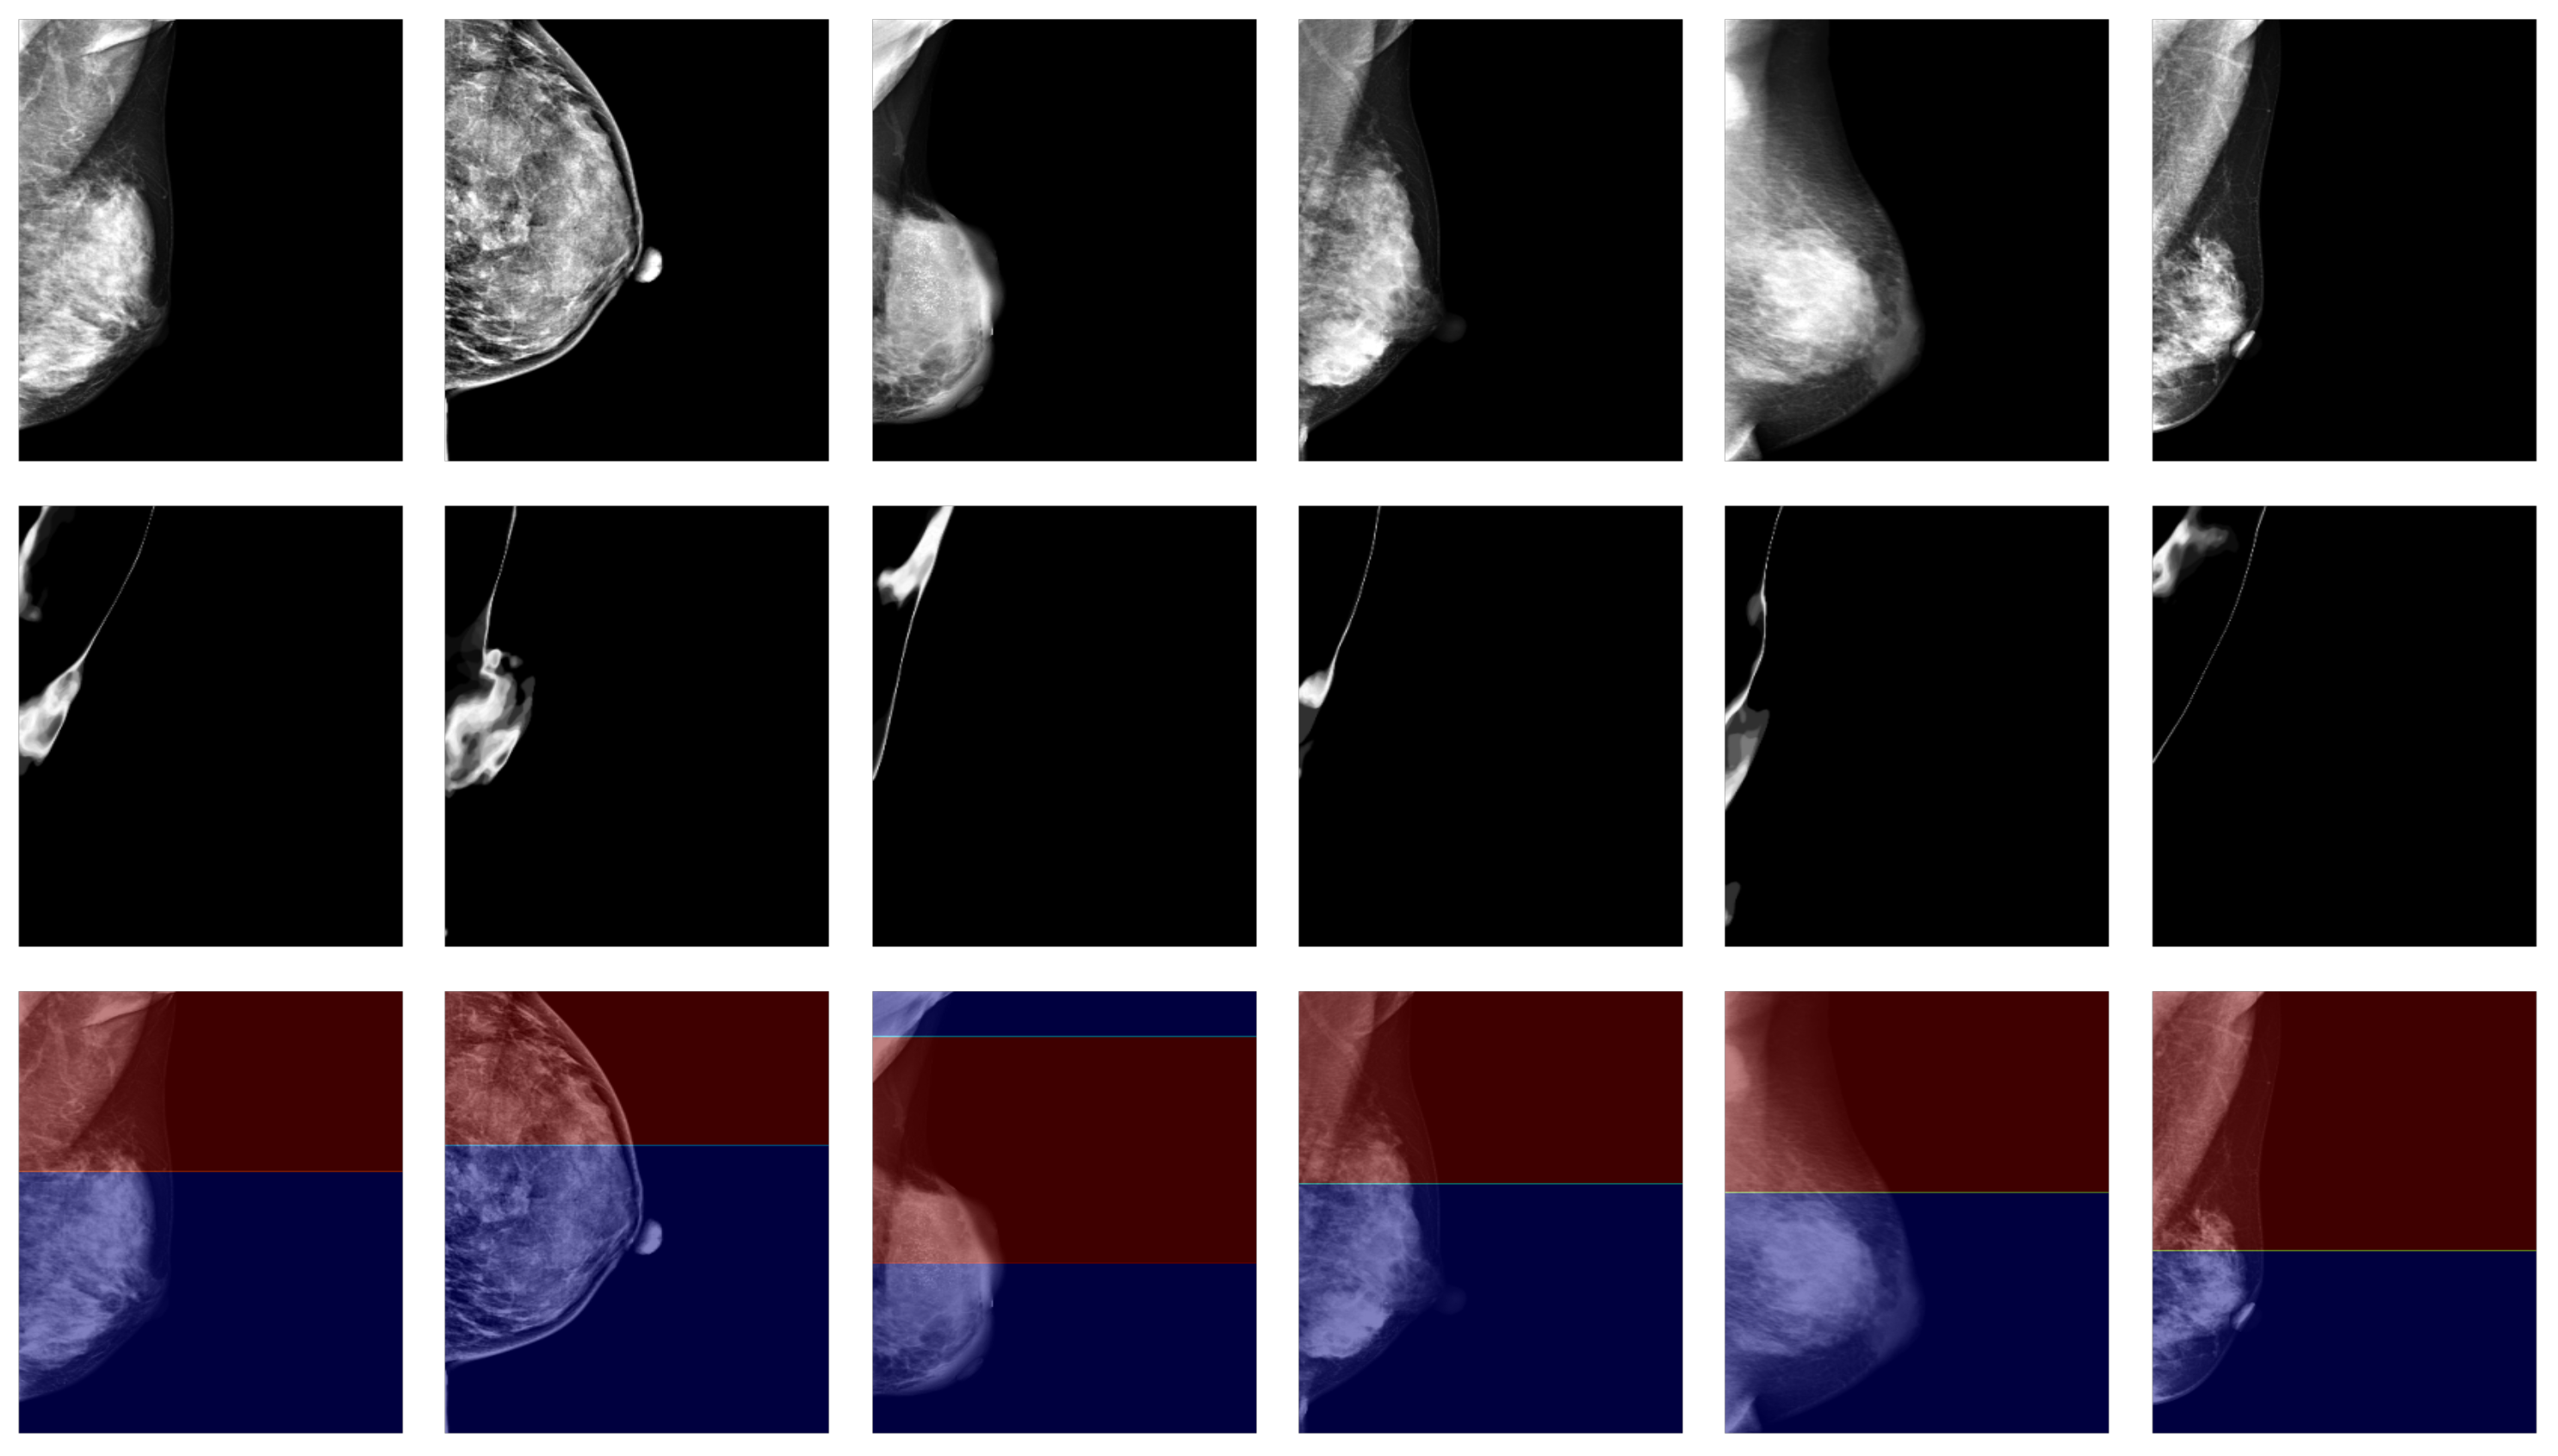

3.2. Qualitative Evaluation

4. Discussion